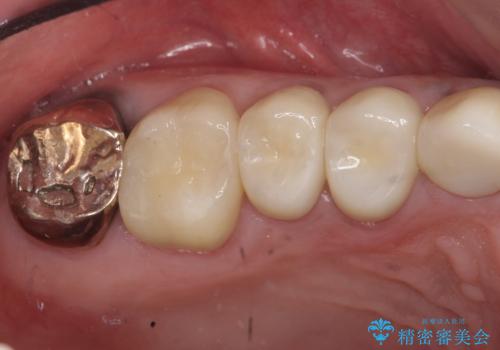

- 歯がない左側でものが咬めず、右側で咬むと歯が痛むので診て欲しいといらっしゃった方の症例です。

根尖病変が認められる歯は再根管治療を行い、歯根が破折していた左上4は抜歯しました。

インプラントは希望されなかったため、左側は1番から7番のロングスパンブリッジによる補綴を行いました。

今回用いたオールセラミッククラウンは、ジルコニアフレームという白い素材の上にセラミックを盛っているため審美性が非常に高いのが特徴です。

またジルコニアは人工ダイヤモンドの材料にも使われているほど高い強度を持っており、そのためオールセラミッククラウンは審美性だけでなく、奥歯やブリッジの補綴も可能とするクラウンです。